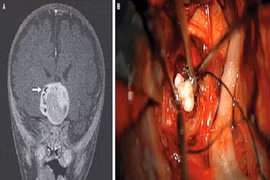

Kỳ lạ răng người xuất hiện trong não trẻ sơ sinh

(Kiến Thức) - Một chiếc răng xuất hiện trong não của trẻ sơ sinh 4 tháng tại Maryland (Mỹ) là trường hợp hiếm gặp.